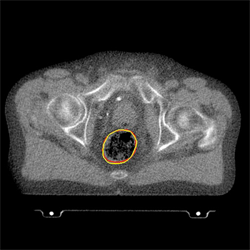

Forest ecologists and medical scientists face a similar problem: to recognise objects in an image automatically. For the medical scientist the objects may be healthy organs in a patient's body that need to be protected from harmful radiation during treatment of cancerous organs. Since an organ might be in a slightly different position at every therapy session, the aim is to create a technique that automatically pin-points its location and then applies the radiation accordingly.

The next task, both for the trees and also for medical imaging, is to pick out the contours that separate one object (say, a tree or an organ) from its surroundings. Again this can be solved using minimisation. Put simply, you look for contours that separate the picture into different regions so that the average numerical value of pixels within any one region equals a prescribed value, which is also found using minimisation.

The position of a patient’s rectum has been pin-pointed (Image: Dr Xiaohao Cai)